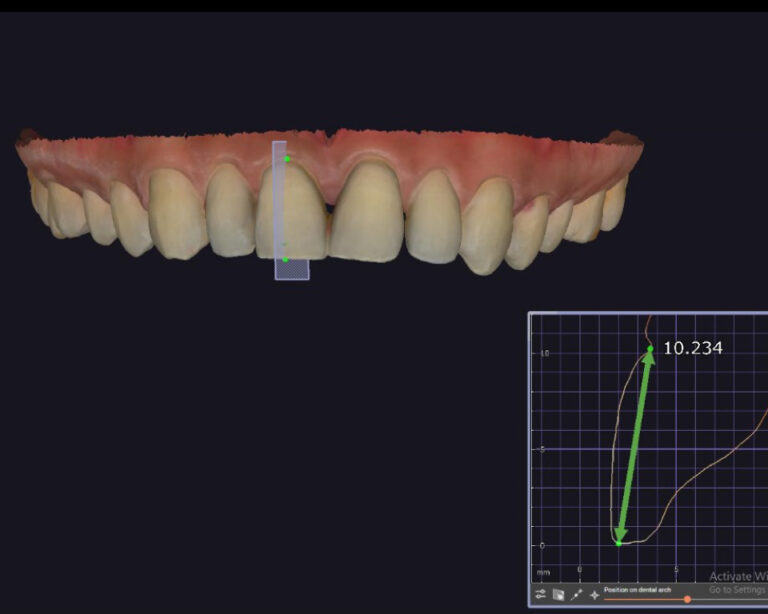

Case of the week